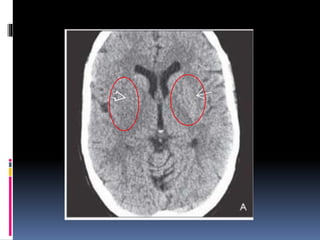

LACUNAR INFARCTS

 Secondary to lipohyalinosis & atherosclerotic occlusion of

perforating branches that arise from the circle of Willis &

peropheral cortical arteries

 Most commonly seen around the basal ganglia,thalami,

internal capsule, deep cerebral white matter & pons.

IMAGING FINDINGS

 Acute infarcts (< 1 week) may not be visible on NECT

 Chronic lacunae may appear as well-defined CSF like

holes .

 Acute lacunae may be visible only on T2W images.

 On T1W decreased signal intensity & on T2W increased

signal intensity is noted.

 On FLAIR fluid is suppressed where as the peripheral

gliosis gives a higher signal intensity

 Blooming is noticed on T2* if associated with chronic

hypertension.

 Acute lacunar infarcts restrict on DWI & may enhance on

T1C+.

LACUNAR INFARCTS  Secondaryto lipohyalinosis & atherosclerotic occlusion of perforating branches that arise from the circle of Willis & peropheral cortical arteries  Most commonly seen around the basal ganglia,thalami, internal capsule, deep cerebral white matter & pons.

• 44.

IMAGING FINDINGS  Acuteinfarcts (< 1 week) may not be visible on NECT  Chronic lacunae may appear as well-defined CSF like holes .  Acute lacunae may be visible only on T2W images.  On T1W decreased signal intensity & on T2W increased signal intensity is noted.  On FLAIR fluid is suppressed where as the peripheral gliosis gives a higher signal intensity  Blooming is noticed on T2* if associated with chronic hypertension.  Acute lacunar infarcts restrict on DWI & may enhance on T1C+.